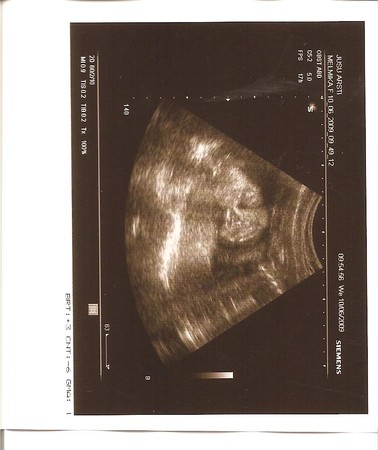

А вот и наше личико

На папу похожа очень-очень!

заигрывала со мной сегодня, такая смешная! Врач подтвердил, что мы девочки! Ура!